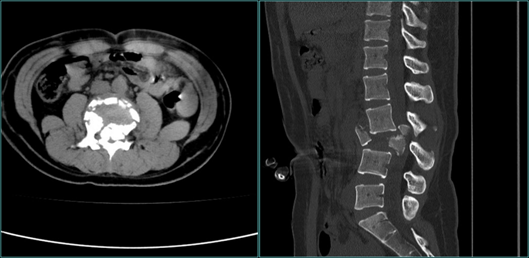

一天,普人民像往常一样有序运转。然而,急诊却并不平静:一位22岁的年轻女孩小郑被120救护车送到了医院急诊。急诊医生简单询问过后,发现她是从高处坠落,导致腰背疼痛,没有办法翻身、起立,现在双下肢处于瘫痪状态。急诊CT显示:腰3椎体爆裂性骨折、腰3双侧椎板骨折。面对这种情况,急诊医生不敢有丝毫耽搁,赶紧将她转到骨科病房住院治疗。

腰椎CT显示

骨科张海龙主任对小郑进行了全面的体格检查,评估了脊柱四肢的运动、感觉和神经反射等情况,并加做了腰椎核磁共振检查。根据影像检查和其他检查结果,发现小郑是腰3椎体爆裂性骨折的骨折碎块压迫脊髓,引起双下肢的不完全性瘫痪,并且合并有马尾神经损伤。